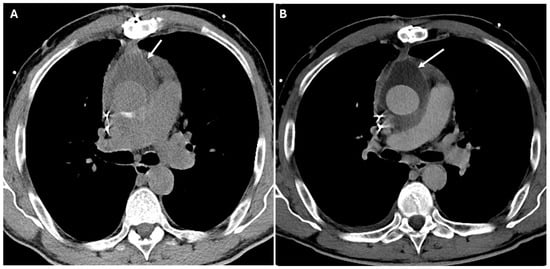

| Perigraft Fluid Collection and Infection | Post-surgical infection | Rim-enhancing fluid collections, intrinsic air | Can progress to graft infection and sepsis |

| Pericardial Effusion and Tamponade | Post-surgical tamponade | Fluid collection in pericardial sac, cardiac chamber compression, septal bowing | May impair cardiac function |

| Bioabsorbable Hemostatic Agents | Used for intraoperative bleeding control. | Heterogeneous masses No air–fluid levels or enhancing walls. Linear arrangement of gas bubbles helps distinguish from infection. | Mimic abscesses, hematomas, tumors or retained foreign bodies. |